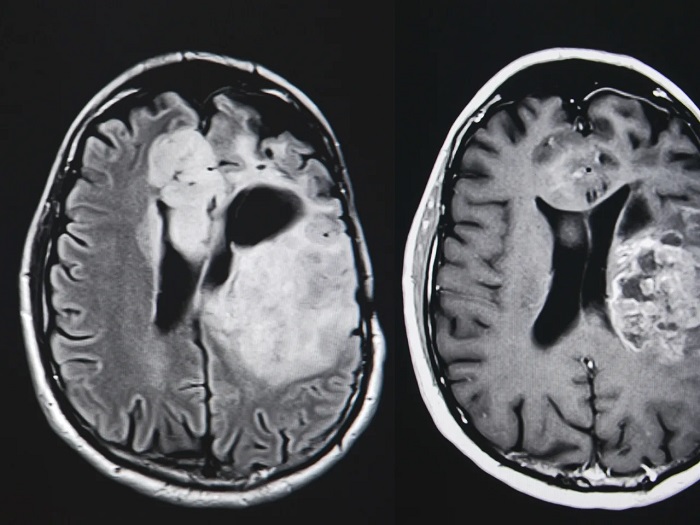

به گزارش اخبار زنده و به نقل از med.news.am، در این پژوهش، محققان دریافتند که مصرف مقادیر زیاد نیکوتینآمید میتواند با تقویت برخی از مسیرهای دفاعی سلولهای ایمنی بدن، آنها را در تشخیص و نابودی سلولهای سرطانی مؤثرتر کند. بهویژه مشاهده شد که این ویتامین موجب فعالتر شدن ماکروفاژها و سلولهای T درون تومور میشود و در نتیجه رشد تودهی سرطانی را کند میکند.

به گفتهی تیم تحقیق، در مدلهای حیوانی، ویتامین B3 توانست نهتنها از گسترش تومور جلوگیری کند، بلکه حساسیت سلولهای سرطانی به شیمیدرمانی را نیز افزایش دهد. این نتیجهها میتواند پایهگذار راهبردهای درمانی نوینی باشد که در آن ترکیب مکملهای تغذیهای با درمانهای سرطان باعث بهبود پاسخ بدن به درمان شود.